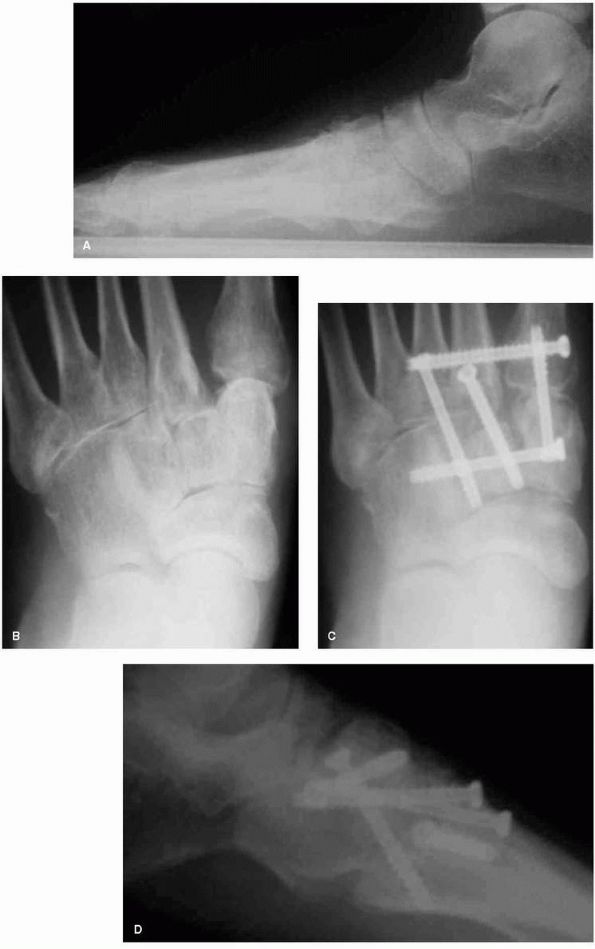

![]() |

|

FIGURE 21-23. Radiographs of midfoot arthrosis. (A)

Lateral views demonstrating midfoot arthritic change and collapse. The normal talus to first metatarsal relationship is altered, consistent with flatfoot deformity. (B) In the AP view, the midfoot arthrosis at the second and third tarsometatarsal joints is noted. (C and D) Postoperative radiographs demonstrating a satisfactory selective midfoot fusion using screw fixation. |